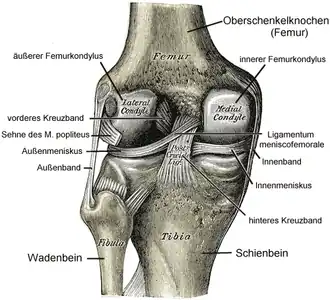

Linkerknie, gezien vanaf de achterzijde | ||||

De voor-achterwaartse stabiliteit in het kniegewricht wordt vooral bereikt door kruislingse banden (de kruisbanden/ligamenta cruciformia) die boven- en onderbeen verbinden. De zijwaartse stabiliteit wordt gewaarborgd door de ligamenta collateralia. Een soepel scharnieren van het bovenbeen ten opzichte van het onderbeen wordt bereikt doordat de knie omvat is in een kapsel en door de aanwezigheid van kraakbeenschijven tussen de scharnierende botdelen (de menisci). Stabiliteit (passief) wordt bereikt door de kniebanden en kruisbanden en (actief) door de bovenbeenspieren.

- De kruisbanden in de knie. Deze voorkomen verschuiving van het boven en onderbeen, voorwaarts of achterwaarts.